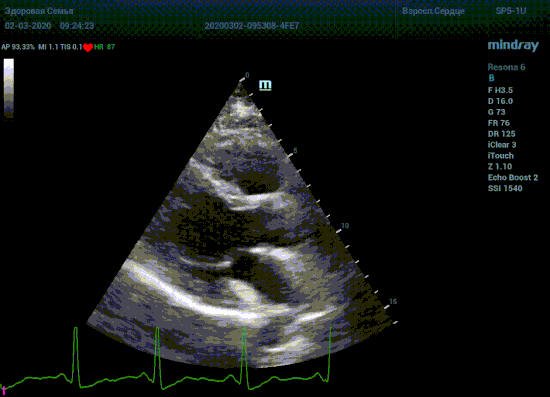

Специалисты в области эхокардиографии прекрасно знают о важности точного и скрупулёзного измерения. Рекомендации зарубежных кардиологических и эхо кардиографических обществ описывают эхокардиографию только под контролем ЭКГ. Многие клиники в России до сих работают без ЭКГ канала, выбирая кадры для измерения «на глазок». Результаты таких исследований менее точны и воспроизводимы, однако роль их очень и очень велика. Часть клиник используют ЭКГ отдельно от прибора, на бумаге. В таком виде для эхокардиографии она бесполезна, по сколку не создает временной карты для измерений.

Подбор подобающей терапии и оценка её динамики на базе расчета массы миокарды рутинная задача эхокардиографии. Для измерения массы нужен кадр конца диастолы. На глазок или точно, по ЭКГ каналу, выбрать диастолу? Гипертрофия миокарда или его ремоделирование? Ремоделирование или норма? Решает каждый измеренный миллиметр, даже каждая его десятая. Лишние доли секунды приведут к началу сокращения миокарда и его утолщению, в результате -гипердиагностика.

Терапия наиболее широкая область применения, однако взрослая кардиохирургия так же важное направление современной медицины. Оперировать аортальный стеноз, или же площадь клапана достаточная? Необходимо рассчитать площадь аортального клапана по уравнению непрерывности потока. Для этого нужно измерить на зуме выносящий тракт левого желудочка (LVOT) в середине систолы. Будем угадывать момент или возьмем середину Т зубца по ЭКГ? Доверимся интуиции при определении показаний к оперативному лечению или науке?

Детская кардиохирургия не исключение. Наиболее актуальная проблема — это дефекты межпредсердной и межжелудочковой перегородок, а также открытый артериальный проток. Не верная оценка гемодинамической значимости приведет к перегрузке правых отделов сердца и ряду осложнений, в случае если не прооперировать вовремя. Отправлять маленького ребенка под нож или подождать пока дефект перегородки зарастет сам? Ждем осложнений или ждать безопасно? На эти вопросы ответит Qp/Qs соотношение, рассчитанное методом эхокардиографии. Для этого необходимо рассчитать ударные объемы выносящих трактов желудочков, опять же на середине систолы – середине Т–зубца ЭКГ.